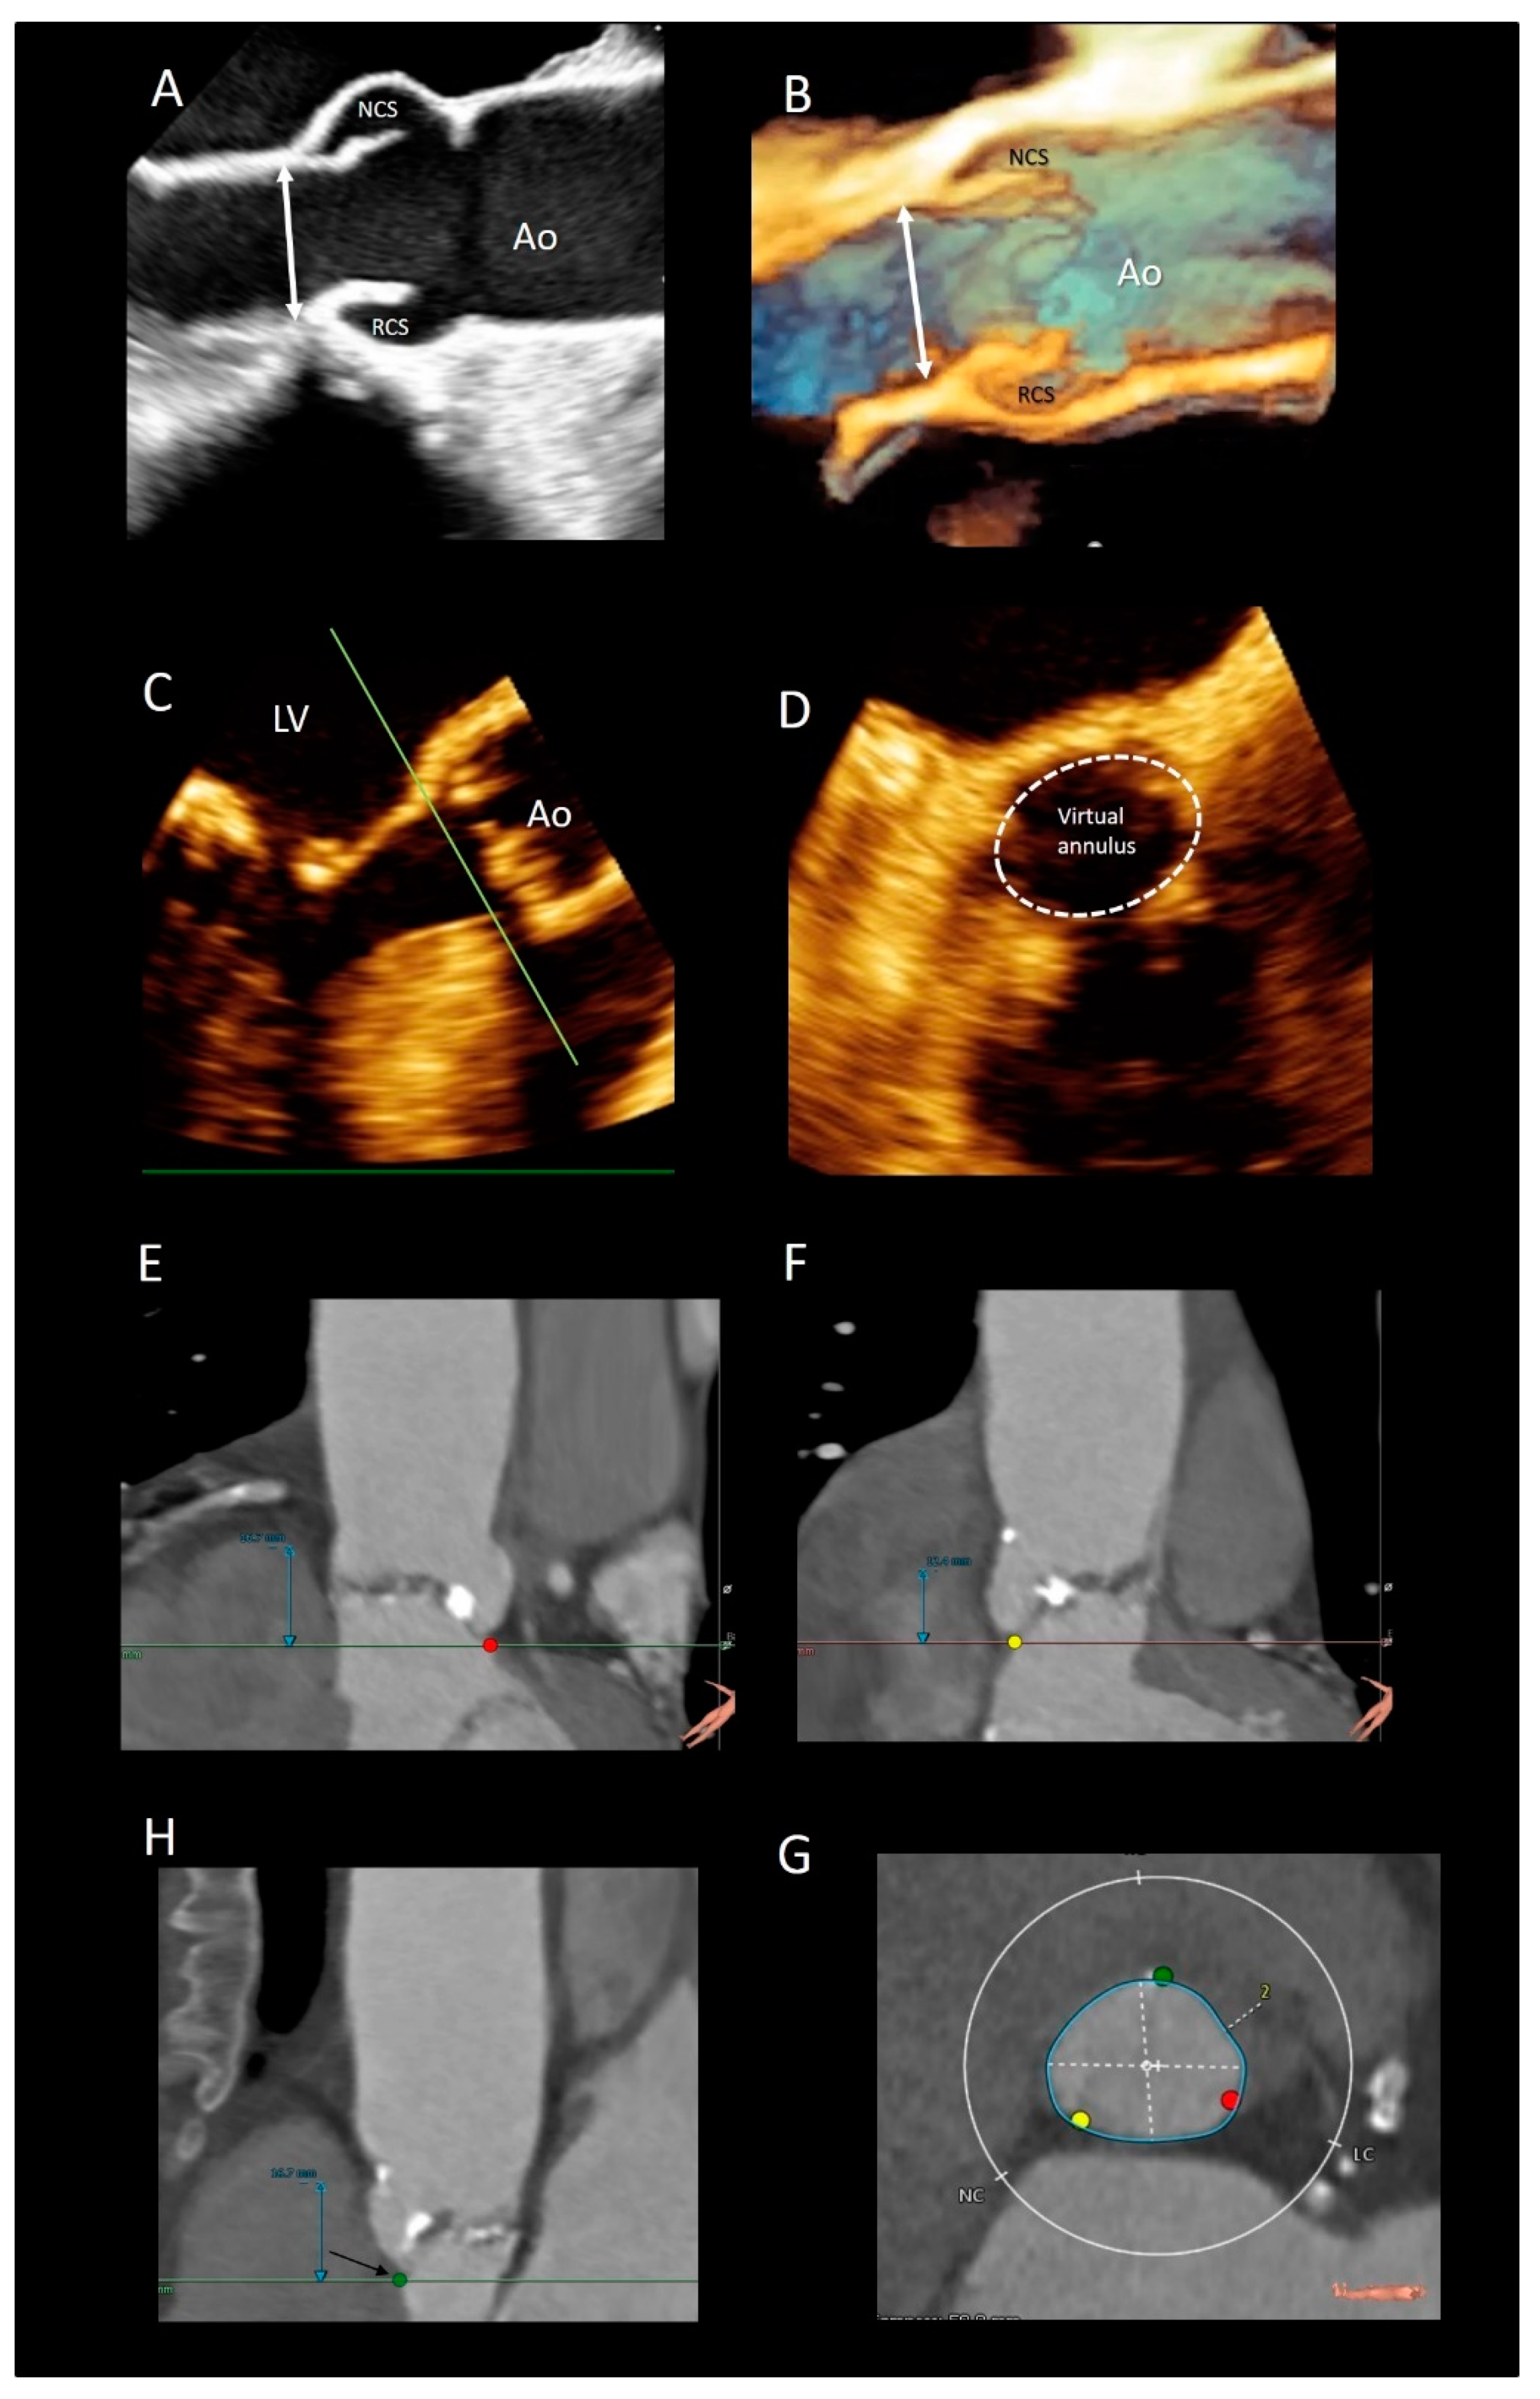

| Ventricular–arterial junction | The term ventricular–arterial junction describes the border between the ventricular myocardium and the fibroelastic structure of the aortic root. Contrary to the right AV junction, where the pulmonary root is entirely supported by the muscular infundibulum, only the left and the right coronary sinuses are partially supported by the myocardium (see text), being the remaining extent of the aortic root supported by fibrous tissue (MS = membranous septum; see text and references [12,13]). | ![]() |

| Cusps, leaflets | The term “cusps” refers to the moving parts of the aortic root. When seen in closed position from the ventricular perspective, this component is similar to the surface of a molar tooth (called cusp). The term is used to describe the structure of the valve (i.e., unicuspidal, bicuspid, and tri-cuspid). Literally the term indicates a pointed end where two curves meet. In the aortic root, it indicates an intact interleaflet triangle with its apex reaching the sinutubular junction. The term leaflet means “small leaf”, which describes a thin, pliable layer. This term perfectly fits the leaflet aspect. N = non-coronary, L = left coronary, R = right coronary leaflets/cusps. | ![]() |

| Commissures | In the anatomy of the aortic root this term refers to the most distal area where the insertions of the leaflets on the aortic wall join each other. | ![]() |

| Aortic annulus | The aortic annulus is the three-dimensional line that follows the hinge line of the leaflets on the aortic wall. This line of dense connective tissue has a crown-shaped appearance (white dotted line). | ![]() |

| Virtual or “echocardiographic” annulus | This term refers to a circumference that joins the lowest points of the leaflet insertion. Although neither anatomically or histologically recognizable, this term has become relevant in the TAVI era. Measurements of this virtual basal plane are used for the sizing of the valve in tricuspid valves. This virtual annuls does not have an anatomic counterpart. | ![]() |

| Surgical annulus | Surgeons fix the prosthetic valves on a circular area lying between the nadirs of the sinuses and midway to the commissures (the aortic prostheses have a flat sewing ring). The term “surgical annulus” refers to this “ring area” and provides a precise reference point when the prosthesis is sutured on “supra” annular position. | ![]() |